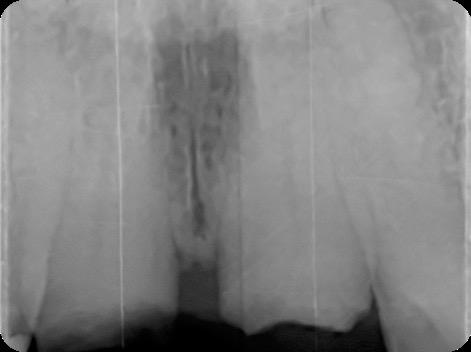

This case was performed by Dr Homa Zadeh, DDS, PhD, a respected leader in periodontology and implant dentistry. Dr Zadeh’s approach emphasizes biologically driven protocols and evidence-based techniques, making this case a strong example of clinical excellence using the Tapered Pro Conical system. It involves the replacement of two front anterior teeth after they fractured off and the full restoration process.

Fig 1. Patient anterior situation. Two anterior crowns fractured off.

Fig 2. Intraoral radiograph indicating tooth structural loss extent.

Fig 5. Central incisors extracted using minimally invasive protocol. Alveolar bone and gingival tissues were intact after extraction

Fig 6. BioHorizons Tapered Pro Conical implants of 3.8 x 15mm placed according to the plan.

Fig 7. Implants immediately after installation.

Fig 8. Scanbody installation for custom abutment and definite restoration fabrication.

Fig 9. Periapical radiograph for verification of proper seating of the scanbodies.